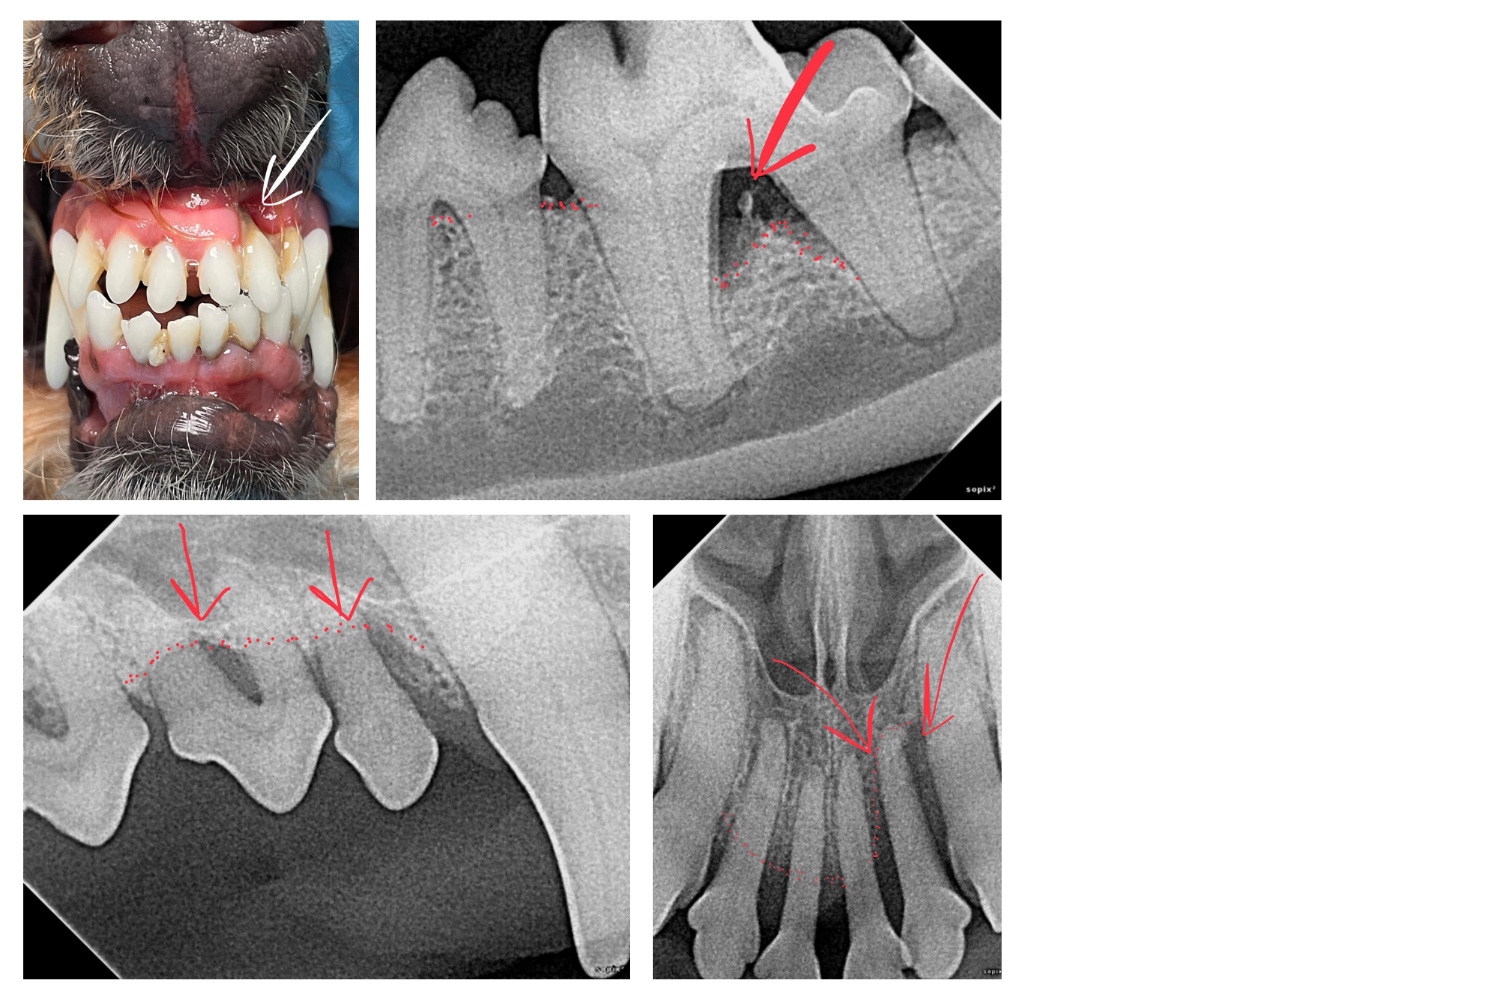

Murphy is a beautiful 8-year-old goldendoodle whose mom came to us for a second opinion on his mouth. It was obvious from the moment we met Murphy’s parents that he was an important part of the family and very well cared for. Unfortunately, Murphy’s mouth was full of signs of advanced and painful periodontal disease. Murphy, like a majority of pets, had suffered in silence for years due to the inappropriate care provided by “nonanesthetic dentals.” Murphy had gingival recession, swollen and red gums, halitosis, mobile teeth, pockets greater than 3 mm, and exposed tooth roots (see Figure 1). These alarming findings of advanced and painful dental disease were documented on a recent nonanesthetic dental and discharge report instructions included to “consider scheduling an anesthetic dental in 6 months.”

Murphy’s mom realized that something just didn’t seem right and was not interested in delaying further appropriate care for her beloved best friend. Without hesitation she scheduled a professional anesthetic dental (dental prophylaxis and dental x-rays) with our team, which allowed Murphy's advanced disease advanced disease to be appropriately assessed and treated. Murphy’s mom, like many other pet parents, was not previously educated on the importance of routine professional dental care and dental homecare. Murphy required extensive oral surgery and surgical extraction of 16 teeth that could have been prevented if the client was properly educated and had care been provided before allowing the disease to progress.